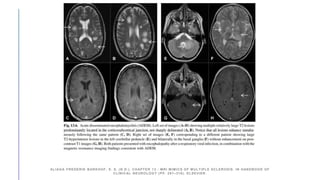

Post circulation

CVS with bilateral

PCA stenosis.

Chronic infarct

and proximal

stenosis of left

MCA.

Multifocal segmental

narrowing (A),

multiple DWI lesions in

different vascular

territories(B),

concentric enhancement of

the M1-segment of the left

middle cerebral artery on

black blood MRI(C),

vessel beading on MRI-

TOF-angiography(D),

bilateral infarctions of

variable size (E),

and intracerebral

hemorrhage (F).

PRIMARY ANGIITIS OFTHE CENTRAL NERVOUS SYSTEM MAGNETIC RESONANC E IMAGING SPECTRUM OF PARENCHYMAL, MENINGEAL, AND VASCULAR LESIONS AT BASE LINE. (N.D.). STROKE. DOI:10.1161/STROKEAHA.116.016194 Post circulation CVS with bilateral PCA stenosis. Chronic infarct and proximal stenosis of left MCA.

Multifocal segmental narrowing (A), multipleDWI lesions in different vascular territories(B), concentric enhancement of the M1-segment of the left middle cerebral artery on black blood MRI(C), vessel beading on MRI- TOF-angiography(D), bilateral infarctions of variable size (E), and intracerebral hemorrhage (F). CAROLIN BEUKE. (N.D.). PRIMARY ANGIITIS OF THE CENTRAL NERVOUS SYSTEM: DIAGNOSIS AND TREATMENT. THER ADV NEUROL DISORD. HTTPS://DOI.ORG/ 10.1177/1756286418785071